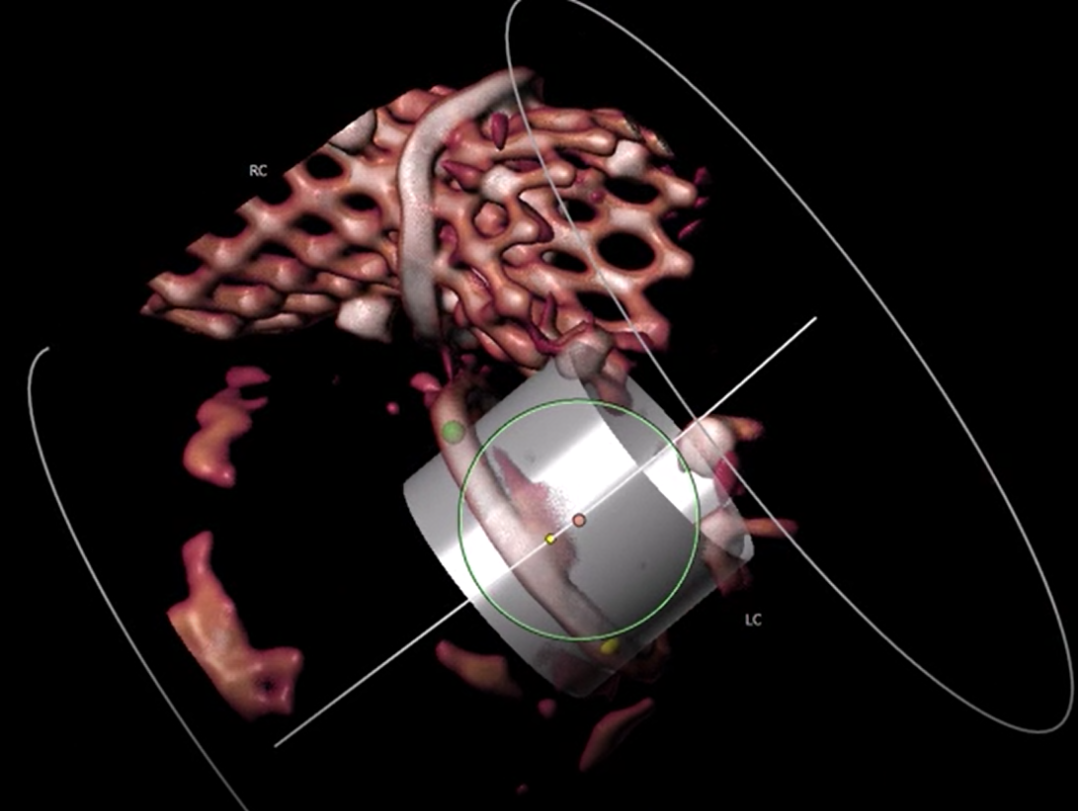

介入瓣膜手术不像开胸手术可以直视瓣膜和相关心脏结构,而且个体化差异较大,透视下瓣膜除了验证钙化之外难以直接观察到瓣膜运动状态,而超声也往往受切面影响不能完整呈现整体心脏结构,因此介入瓣膜术中复杂病例的解剖定位不清楚会增加手术难度和风险。手术虚拟融合技术则充分利用三维CT扫描的详细信息,结合手术中透视下心脏结构的定位,两者相结合可以在手术野中虚拟出来心脏三维结构,直接在透视显示器中融合显现出来,大大增加了主刀医师对瓣膜和心脏周边结构细节完整性的呈现。而且介入瓣膜手术中,随着投射角度变和、手术床位置的调整,虚拟融合影像会自动随之而融合,随着投射角度和投射视野改变而变和,术者使用非常方便有效。

安贞医院心外科瓣膜中心(九病区)张海波教授团队率先国内开展介入瓣膜手术前的3D打印和三维影像虚拟模拟技术,对复杂结构病例进行术前充分多维度的分析,成功完成了多瓣膜生物瓣毁损的双瓣介入瓣中瓣、大动脉转位的生物瓣毁损介入手术、继往二尖瓣置换后的主动脉瓣重度狭窄、严重横位心二叶畸形、主动脉瓣四叶畸形、冠脉位置低至3.5mm等许多解剖结构复杂的介入瓣膜手术。再次基础上,近年来经过与公司研发团队多次筹备和反复尝试,在瓣膜中心李岩、王坚刚,麻醉卢家凯、武威,手术室许斌,影像科徐磊,超声张纯,体外循环黑飞龙、杨景,重症监护贾明等多学科协助下,成功在心脏主动脉瓣狭窄、主动脉瓣关闭不全、三尖瓣、二尖瓣生物瓣毁损等多种心脏瓣膜介入手术中利用手术虚拟影像融合技术,为国内首家全面完成手术虚拟融合介入瓣膜手术的中心,多项融合技术为国内首先完成。术中虚拟影像技术大大简化介入瓣膜手术流程,进一步提高了介入瓣膜手术精准度的把控,提高了手术安全性和成功率。